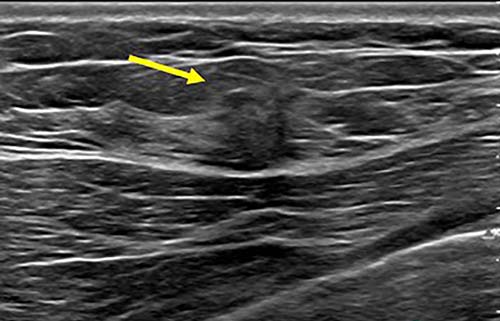

Figure 3. Spot on right mediolateral oblique (side angle) view. Area of distortion persists on additional mammographic views, and a mass is identified on subsequent breast ultrasound. Ultrasound guided biopsy was performed and revealed nuclear grade 1 invasive ductal carcinoma.

Figure 4. Breast ultrasound image. Area of distortion persisted on additional mammographic views, and a mass is identified on subsequent breast ultrasound. Ultrasound guided biopsy was performed and revealed nuclear grade 1 invasive ductal carcinoma.